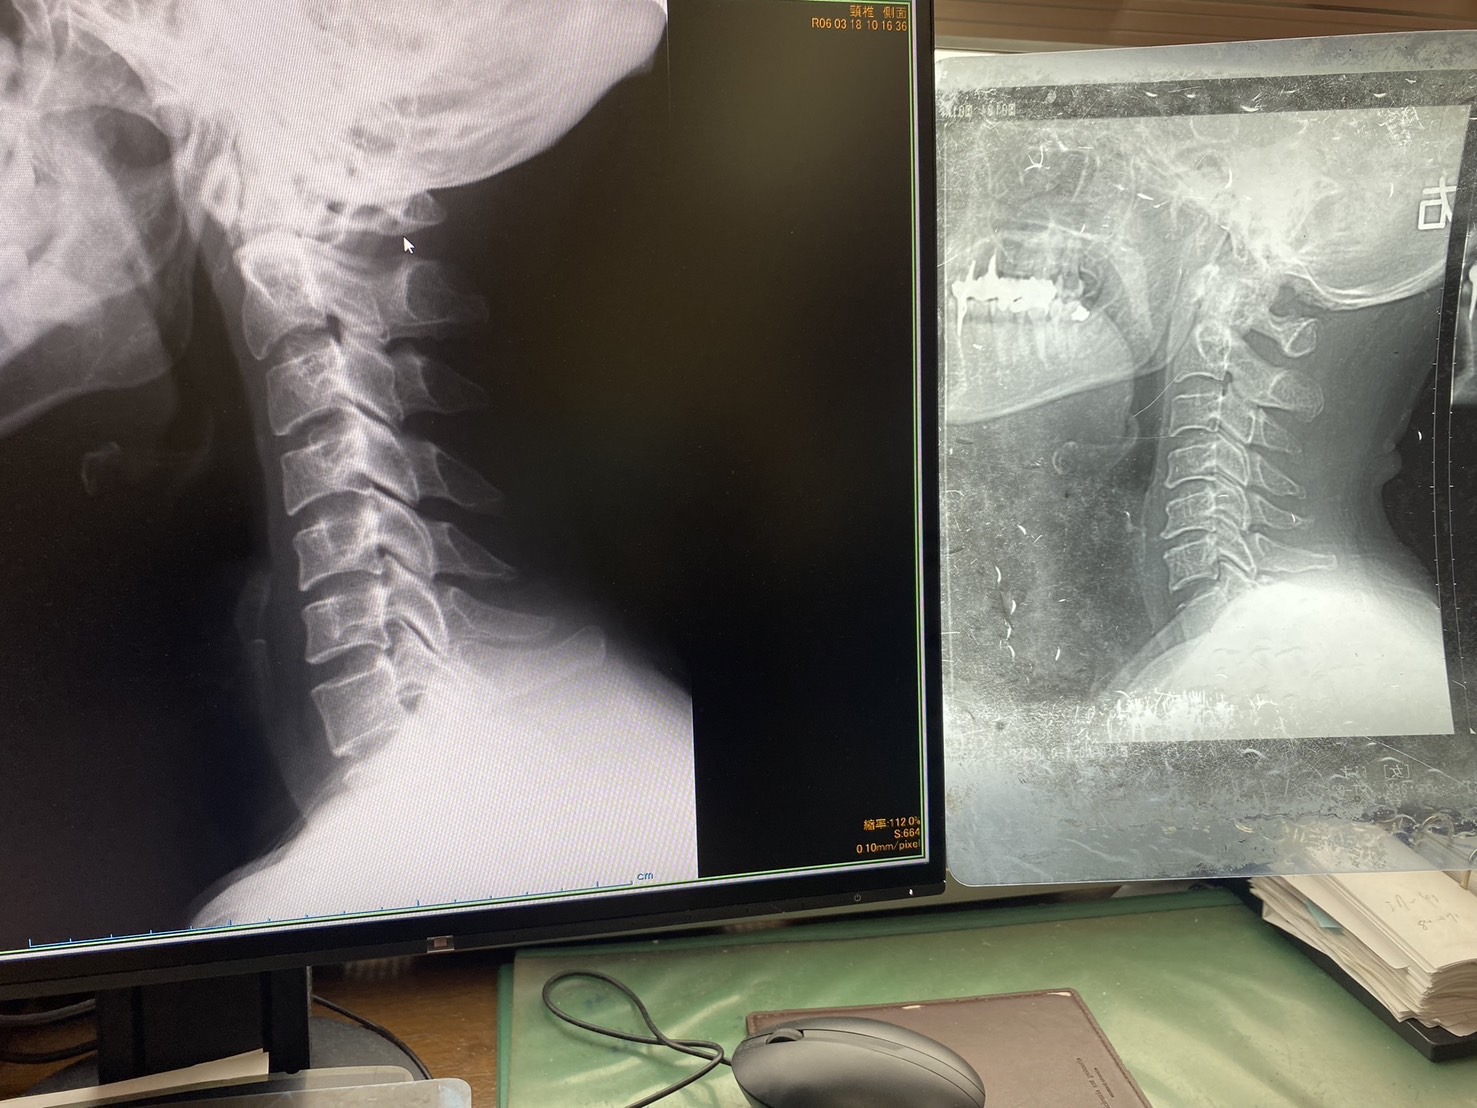

頚椎のヘルニアかな?っと整形外科に行くとなんと、

すんごいストレートネックでしたw

※右が通常です